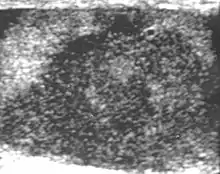

Embryonal cell carcinomas, a more aggressive tumor than seminoma usually occurs in men in their 30s. Although it is the second most common testicular tumor after seminoma, pure embryonal cell carcinoma is rare and constitutes only about 3 percent of the nonseminomatous germ cell tumors. Most of the cases occur in combination with other cell types. At ultrasound, embryonal cell carcinomas are predominantly hypoechoic lesions with ill-defined margins and an inhomogeneous echotexture. Echogenic foci due to hemorrhage, calcification, or fibrosis are commonly seen. Twenty percent of embryonal cell carcinomas have cystic components. The tumor may invade into the tunica albuginea resulting in contour distortion of the testis [Fig. 4].

Teratoma Although teratoma is the second most common testicular tumor in children, it affects all age groups. Mature teratoma in children is often benign, but teratoma in adults, regardless of age, should be considered malignant. Teratomas are composed of all three germ cell layers, i.e. endoderm, mesoderm and ectoderm. At ultrasound, teratomas generally form well-circumscribed complex masses. Echogenic foci representing calcification, cartilage, immature bone and fibrosis are commonly seen [Fig. 5]. Cysts are also a common feature and depending on the contents of the cysts i.e. serous, mucoid or keratinous fluid, it may present as anechoic or complex structure [Fig. 6].